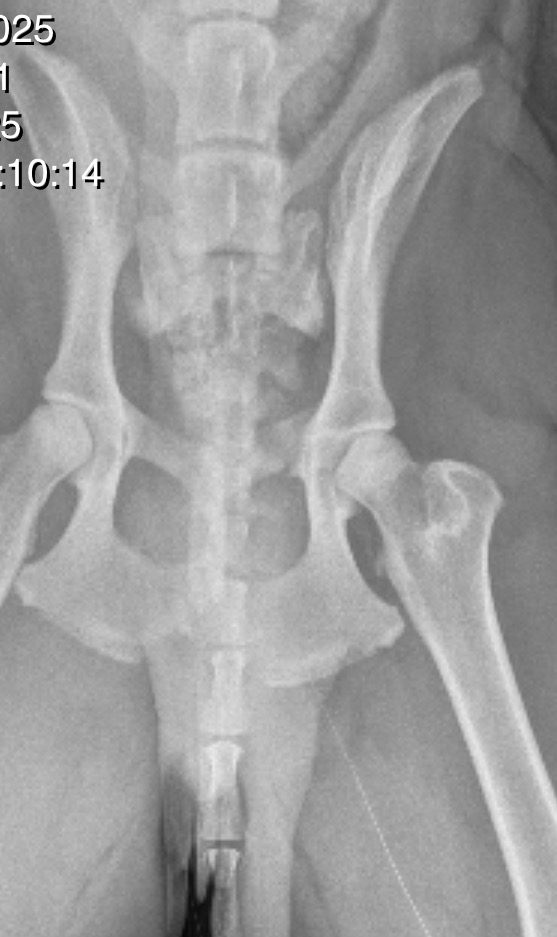

Sadly, Duke has suffered a horrific accident. A backhoe tire rolled back onto him, leaving him with a broken pelvis and bilateral sacroiliac joint displacement. This painful injury has made it nearly impossible for him to walk or play like the happy pup he used to be.

The veterinarians say Duke needs specialist orthopedic surgery to reset and stabilize his joints with screws. Without this surgery, Duke may never walk again. The cost of this life-changing procedure is estimated at $8,000—far more than I can manage alone.